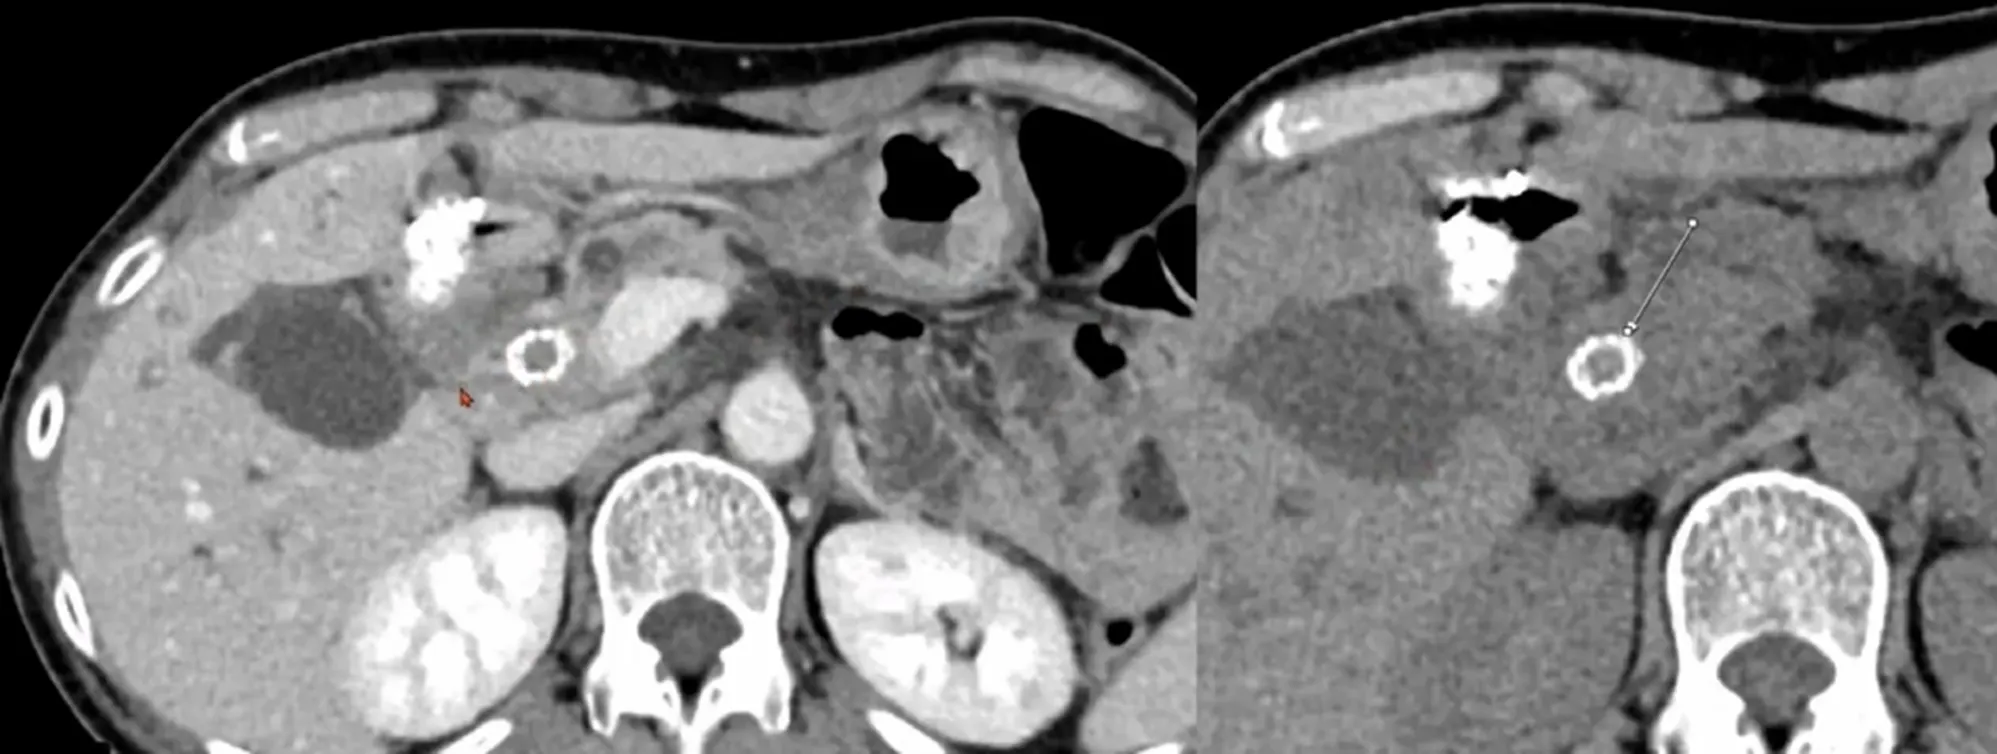

Case 10-1

•

M/94

C/C: abdominal pain

Hx : sigmoid colon cancer s/p anterior resection , AAA s/p EVAR, s/p PTGBD insertion

Lab: CRP 14.9mg/dL, Hb 9.6g/dL

Contained rupture